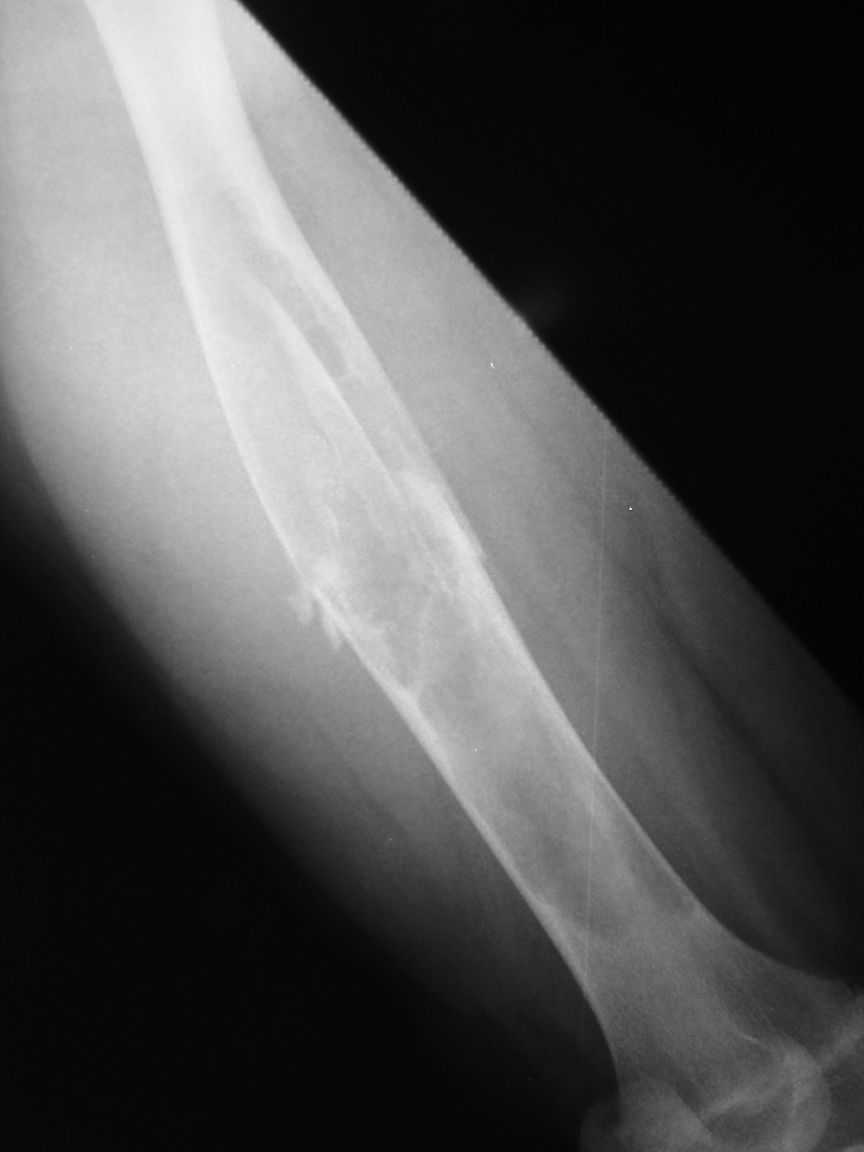

Re: Pathological fracture femur

Most likely fibrous dysplasia, we had the same case but younger age patient 4 years ago treated by uniplanar ext fix followed by percut. curretage and bone marrow injection and healed well.

at this age IMN can solve the problem .

I agree that this case is fibrous dysplasia.

As a method of treetment I propose removal of fibous tissue and cavity allografting, including frozen cortical long graft as an intramedullary nailing. I think it is a good decision without using of any metal construction.